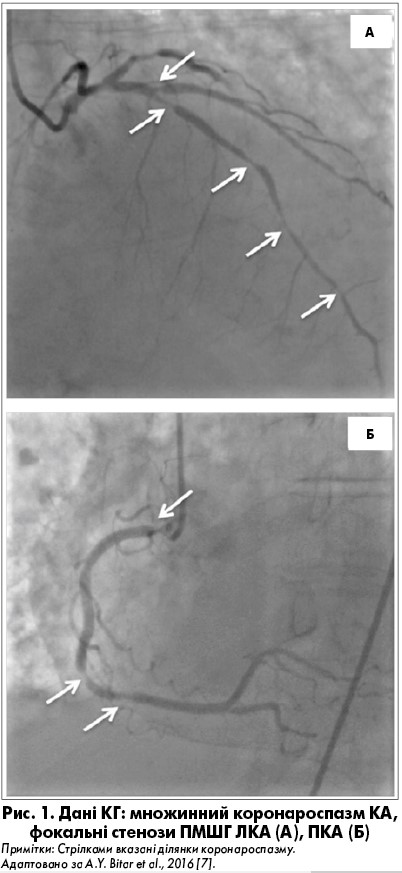

У літературі є повідомлення про розвиток ГКС, що ускладнився фібриляцією шлуночків, зупинкою серця, а про проведенні КГ виявлений коронароспазм передньої міжшлуночкової гілки (ПМШГ) лівої КА (ЛКА) та правої КА (ПКА), що минув після інтракоронарного введення нітрогліцерину [6]. Крім того, описаний розвиток ГКС з елевацією сегмента ST, що ускладнився кардіогенним шоком як першим проявом ЕГПА. У пацієнтки за даними КГ (рис. 1) виявлений множинний спазм КА (ПМШГ ЛКА, першої діагональної, проміжної гілок, ПКА, задньої міжшлуночкової гілки ПКА). Після інтракоронарного введення верапамілу та нітрогліцерину значно зменшився стеноз ПКА, а ПМША та її гілок – незначно, тому проведено імплантацію елютинг-стентів у ПМШГ ЛКА і першу діагональну гілку ЛКА. Проте на тлі приймання нітратів тривалої дії та антагоністів кальцію у пацієнтки відмічали стенокардію, яка пройшла після призначення ГК [7].